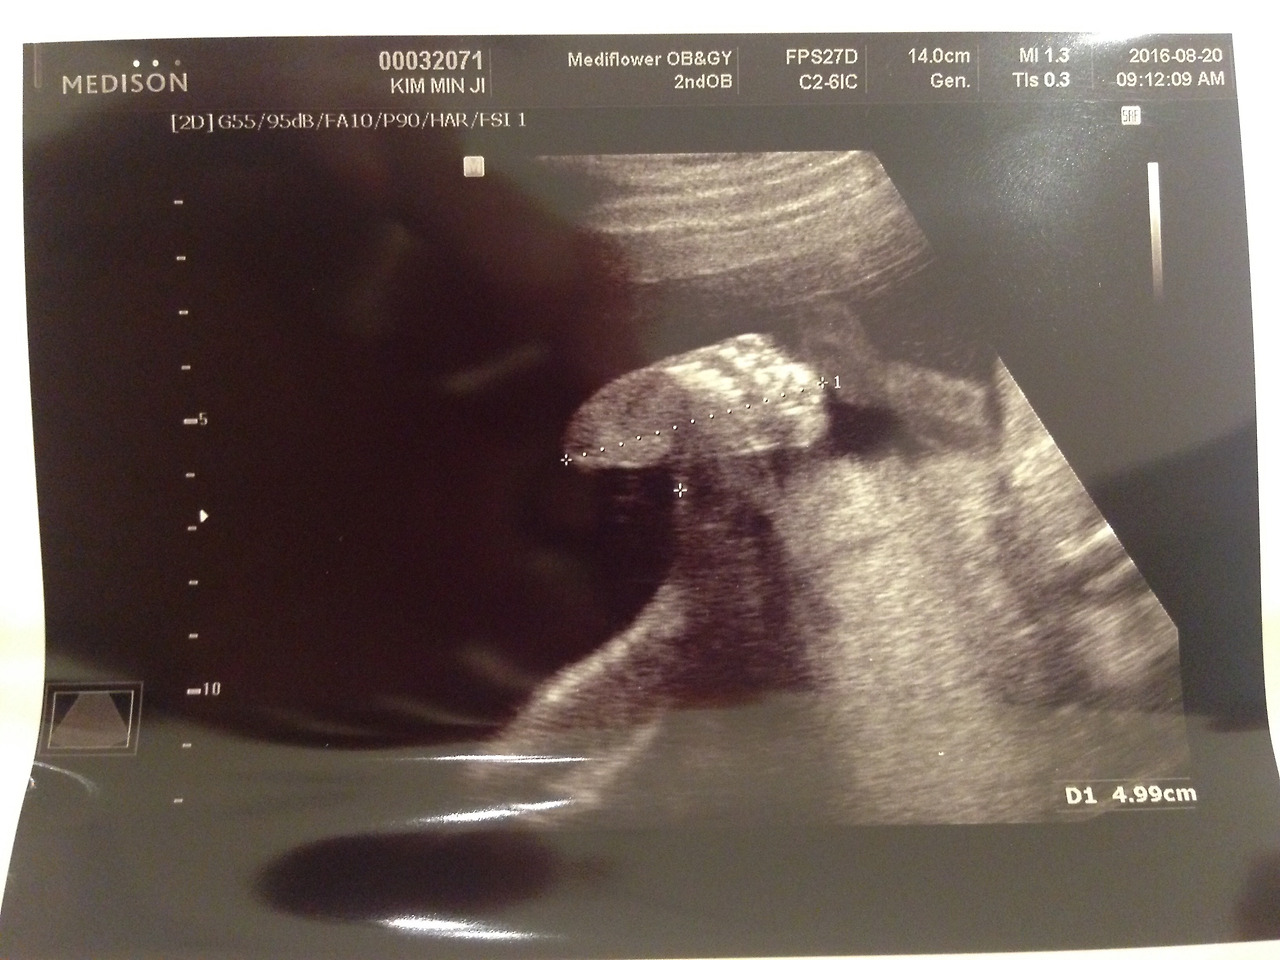

지난번 자세히 못 본 심장을 먼저 보니 2심방 2심실이 뚜렷이 구분되고 아주 잘 뛴다. 등뼈와 갈비뼈가 촘촘하고 위도 잘 있다. 머리 둘레도 좋고, 키도 좋고, 팔다리 다 좋다. 양수가 충분해서 아이가 활동하기 좋은 환경이라고 한다. 근종들(3개)은 산도와 떨어져 있어 출산에 지장이 없을 것이라는 말에 적잖이 안심이 됐다. 다만 위치가 통증이 있을 수도 있다고... 음식 잘 먹고 족욕 꾸준히 하기로 했다.

사진에는 맛동산 1/4개 크기의 '꼬추'가 보였다. 땅콩 같기도 한 그것.